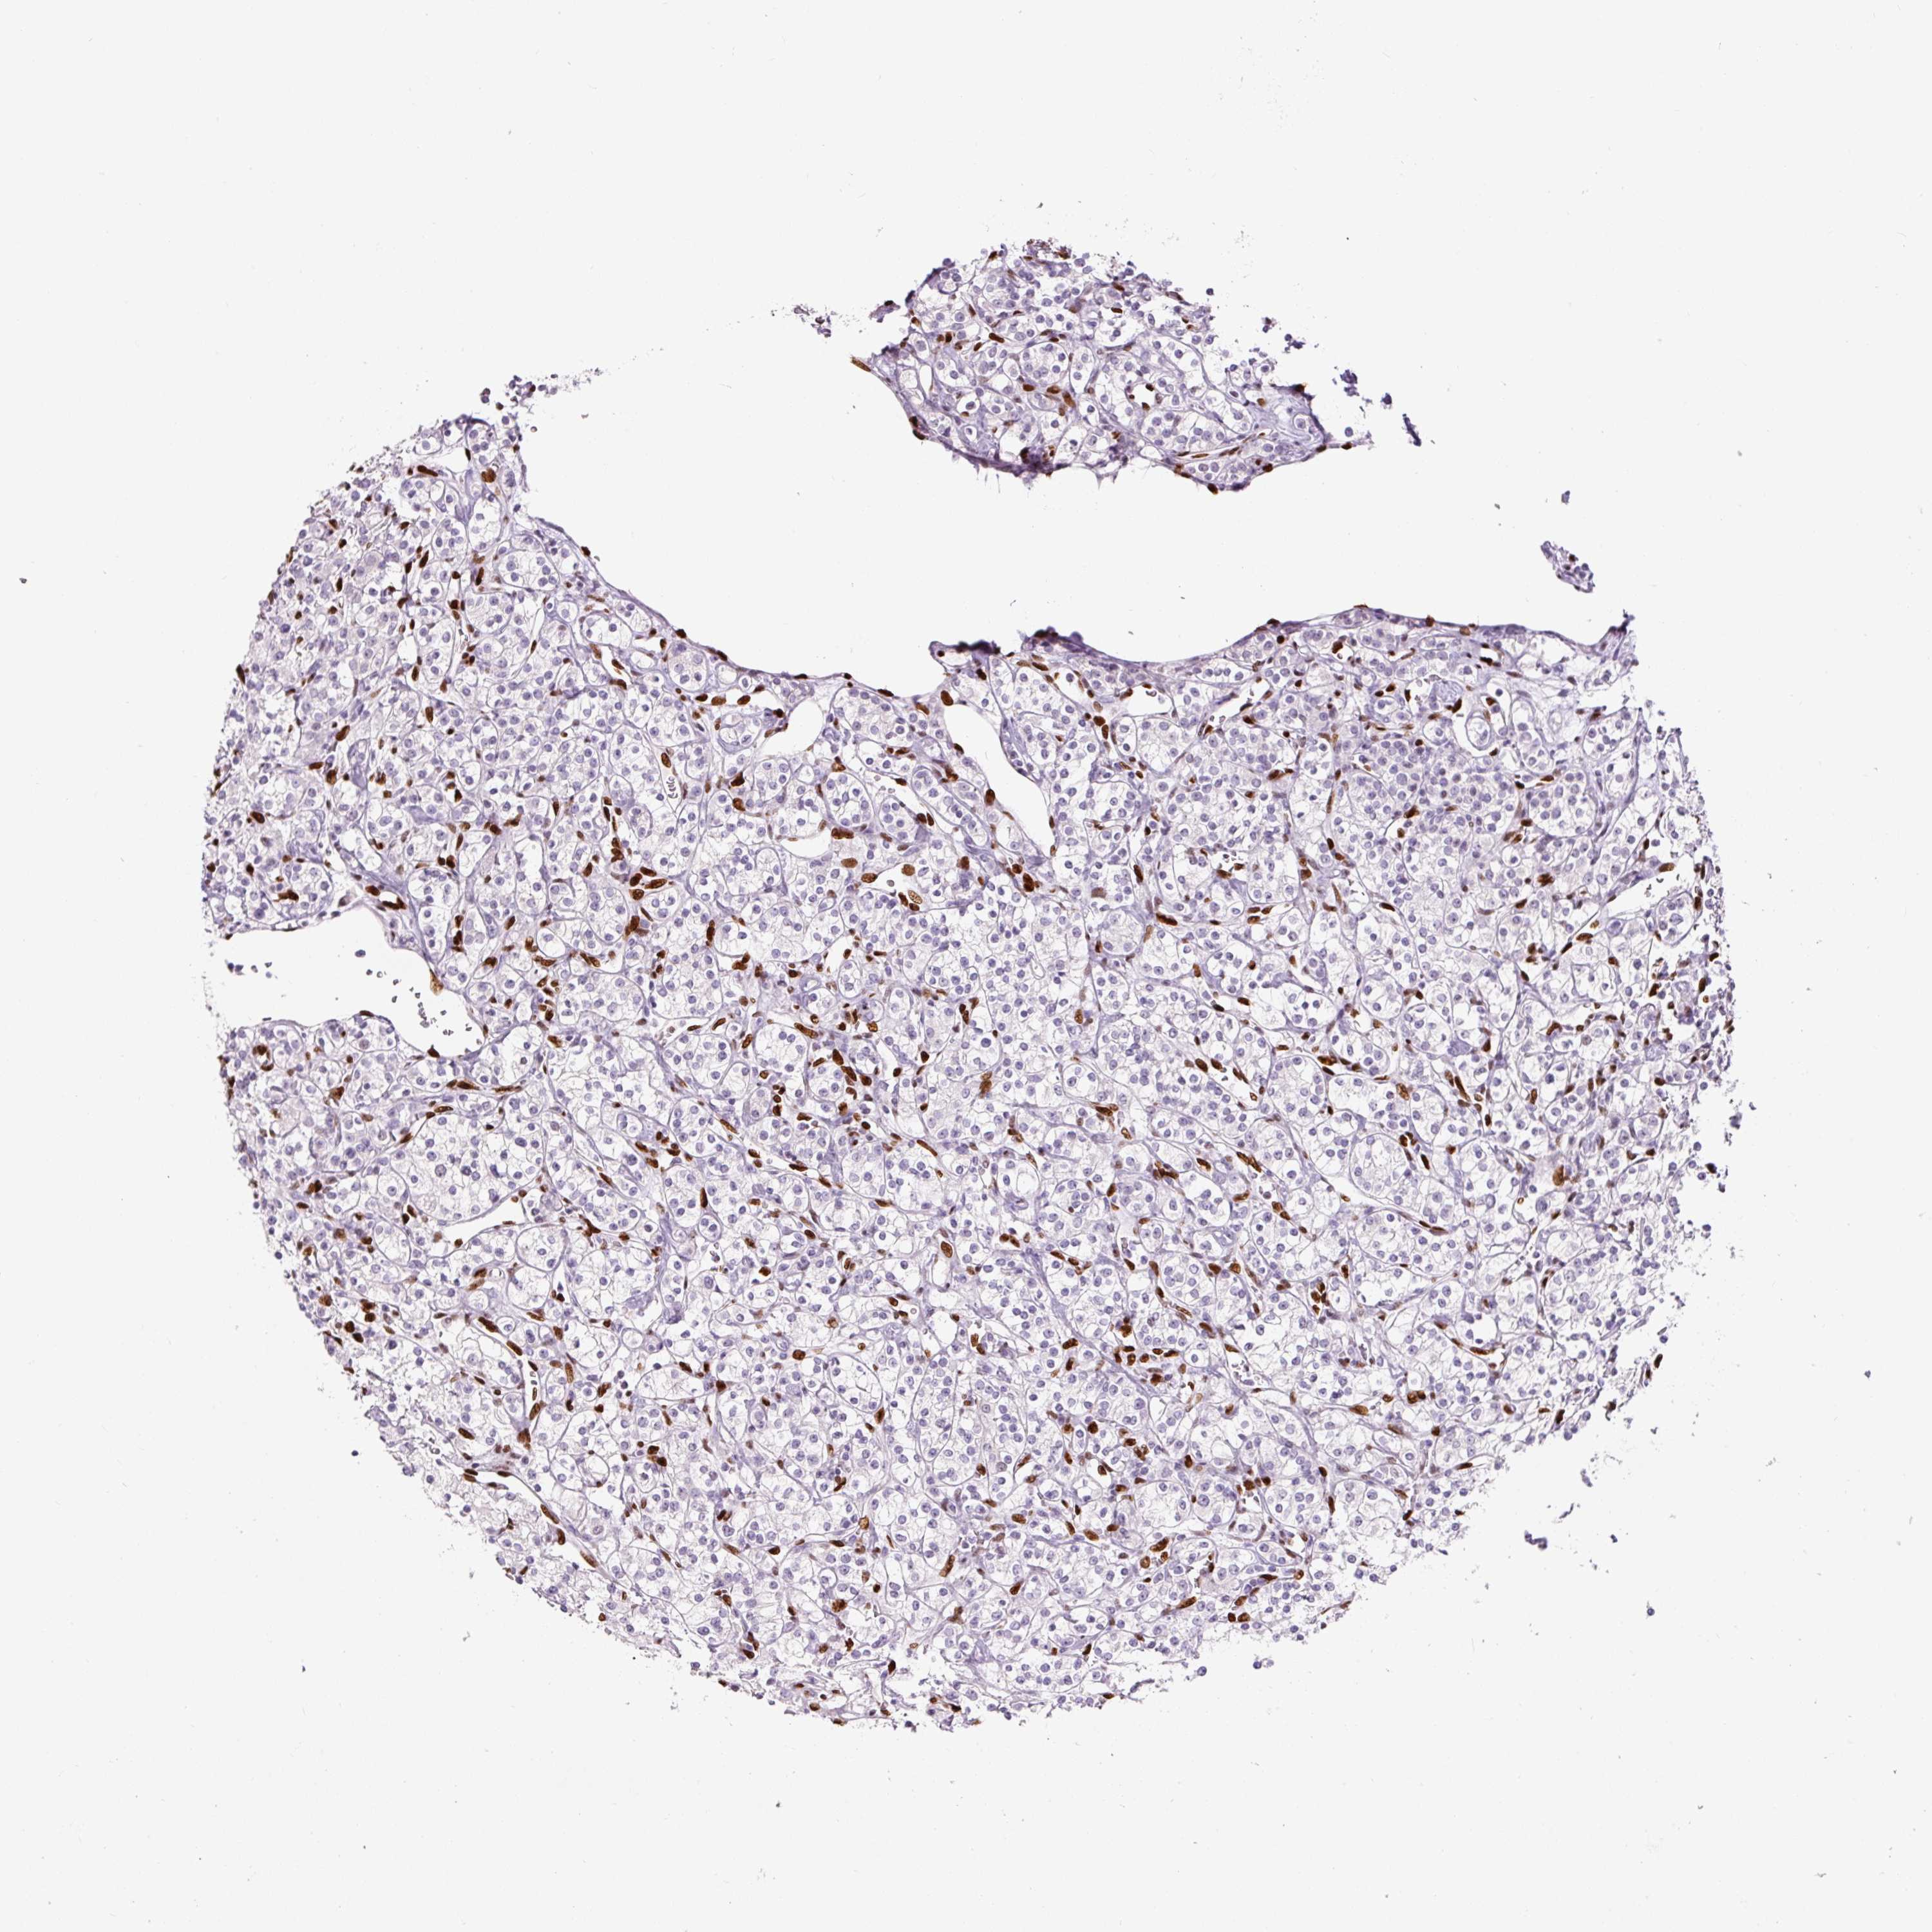

KIDNEY CHROMOPHOBE (TCGA) - Interactive survival scatter ploti

The Survival Scatter plot shows the clinical status (i.e. dead or alive) for all individuals in the patient cohort, based on the same data that underlies the corresponding Kaplan-Meier plots. Patients that are alive at last time for follow-up are shown in blue and patients who have died during the study are shown in red.

The x-axis shows the expression levels (FPKM) of the investigated gene in the tumor tissue at the time of diagnosis. The y-axis shows the follow-up time after diagnosis (years). Both axes are complimented with kernel density curves demonstrating the data density over the axes. The top density plot shows the expression levels (FPKM) distribution among dead (red) and alive patients (blue). The right density plot shows the data density of the survived years of dead patients with high and low expression levels respectively, stratified using the cutoff indicated by the vertical dashed line through the Survival Scatter plot. This cutoff is automatically defined based on the FPKM cutoff that minimizes the p-score. The cutoff can be changed by dragging the vertical line or by entering a cutoff value in the square labeled "Current cut-off".

Under the Survival Scatter plot the p-score landscape (black curve; left axis) is shown together with dead median separation (red curve; right axis). Dead median separation is the difference in median mRNA expression between patients who have died with high and low expression, respectively. It is calculated as follows: median FPKM expression of dead patients with high expression - median FPKM expression of dead patients with low expression. This is intended to aid the user in visually exploring custom cutoffs and the associated p-scores and dead median separation.

Individual patient data is displayed and can be filtered by clicking on one or more of the category buttons on the top of the page. Categories describing expression level and patient information include: high, low, alive, dead, female, male and tumor stages. The scale of the x-axis can be toggled between linear and log-scale by clicking on the "x log" button. Mouse-over function shows TCGA ID, patient information and mRNA expression (FPKM) for each patient.

& Survival analysisi

Kaplan-Meier plots summarize results from analysis of correlation between mRNA expression level and patient survival. Patients were divided based on level of expression into one of the two groups "low" (under cut off) or "high" (over cut off). X-axis shows time for survival (years) and y-axis shows the probability of survival, where 1.0 corresponds to 100 percent.

ZEB1 is not prognostic in Kidney Chromophobe (TCGA)

Best expression cut offi

Based on the FPKM value of each gene, patients were classified into two groups and association between prognosis (survival) and gene expression (FPKM) was examined. The best expression cut-off refers the FPKM value that yields maximal difference with regard to survival between the two groups at the lowest log-rank P-value. Best expression cut-off was selected based on survival analysis .

When clicking on this number, the vertical dashed line indicating cut-off, the interactive survival plot, and the Kaplan-Meier curve will be adjusted to show results based on the best expression cut-off.

: 1.74

Median expressioni

Median expression refers to the median FPKM value calculated based on the gene expression (FPKM) data from all patients in this dataset. When clicking on this number, the vertical dashed line indicating cut-off, the interactive survival plot, and the Kaplan-Meier curve will be adjusted to show results based on the median expression.

: N/A

Median follow up timei

Median follow up time refers to the median time (years) after diagnosis with this type of cancer, based on clinical data from all patients in this dataset.

P scorei

Log-rank P value for Kaplan-Meier plot showing results from analysis of correlation between mRNA expression level and patient survival.

N/A

5-year survival highi

5-year survival for patients with higher expression than the expression cutoff.

For melanoma and glioma, 3-year survival is shown.

5-year survival lowi

5-year survival for patients with lower expression than the expression cutoff.

TCGA RNA samplesi

RNA-seq data is reported as average FPKM (number Fragments Per Kilobase of exon per Million reads), generated by the The Cancer Genome Atlas (TCGA) .

Normal distribution across the dataset is visualized with box plots, shown as median and 25th and 75th percentiles. Points are displayed as outliers if they are above or below 1.5 times the interquartile range. FPKM values of the individual samples are presented next to the box plot.

Average pTPM 4.1

Number of samples 64